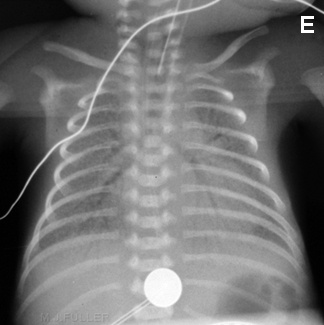

Hérnia diafragmática congênita

Do acervo de Ponthenkandath Sasidharan, MD; usado com permissão